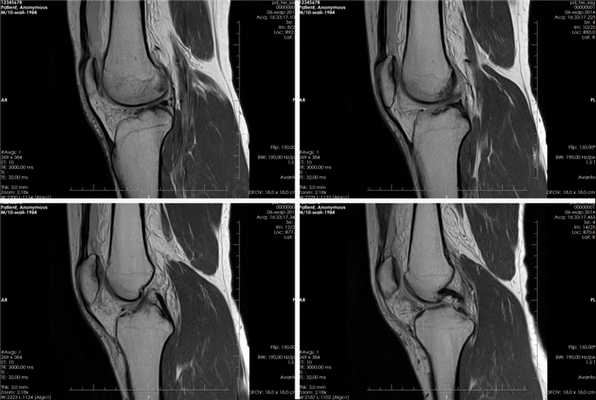

(Слева) На сагиттальной КТ с реформатированием у этого же пациента определяется оскольчатый перелом головки лучевой кости и хронический задний подвывих лучеголовчатого сустава.

(Справа) На сагиттальном изображении с реформатированием более медиально у этого же пациента определяется хронический задний подвывих локтевого сустава и перелом венечного отростка со смещением. Вывих предплечья, сочетающийся с переломами головки лучевой кости и венечного отростка называется «несчастная триада» в связи с плохим прогнозом. (Слева) На передне-задней рентгенограмме у спортсмена 14 лет после травмы локтевого сустава определяется заднебоковой вывих локтевого и лучеголовчатого суставов. По медиальному краю сустава имеется отломок без заметного донорского участка.

(Справа) На боковой рентгенограмме у этого же пациента более четко определяется вывих и виден ущемленный отломок. Хорошо определяемые края отломка и возраст пациента являются признаками возможного отрыва медиального надмыщелка плечевой кости. (Слева) На фронтальной КТ с реформатированием у этого же пациента визуализируется ущемленный отломок и донорский участок медиального надмыщелка. Предполагается, что край надмыщелка покрыт гладким кортикальным слоем; отсутствие прилежащего к нему ожидаемого центра оссификации надмыщелка следует рассматривать как основание для постановки этого диагноза.

(Справа) На сагиттальной КТ с реформатированием у этого же пациента определяется выраженный кортикальный слой ущемленных отломков медиального надмыщелка, что помогает подтвердить их происхождение.

(Слева) На боковой рентгенограмме определяется слабовыраженная неконгруэнтность локтевого сустава. Лучевая кость и головка мыщелка плечевой кости расположены нормально Перелом не виден.

(Справа) На передне-задней рентгенограмме у этого же пациента определяется боковой вывих локтевого и лучеголовчатого суставов. Прямой боковой вывих предплечья является очень необычным явлением. Костные отломки, вероятно, отходят от латерального мыщелка. (Слева) На рисунке показан задний вывих локтевого отростка и лучевой кош с разрывом комплекса локтевой коллатеральной связки. Поперечный пучок остается интактным.

(Справа) На фронтальной МРТ Т2ВИ FS после вывиха предплечья определяется разрыв переднего пучка локтевой коллатеральной связки с отрывом выступающего бугорка и разрывом кольцевой и лучевой коллатеральной связки и латеральной локтевой коллатеральной связки. (Слева) На передне-задней рентгенограмме ребенка определяется полное смещение дистального эпифиза плечевой кости от дистальной трети диафиза плечевой кости. Чтобы отличить его от вывиха плеча, следует обратить внимание на сохранение нормального расположения луче-головчатого и локтеблокового суставов.

(Справа) На боковой рентгенограмме шестилетнего ребенка без травмы в анамнезе, который жаловался на ограниченную пронацию локтевого сустава, определяется врожденный вывих головки лучевой кош Это находка двусторонняя.